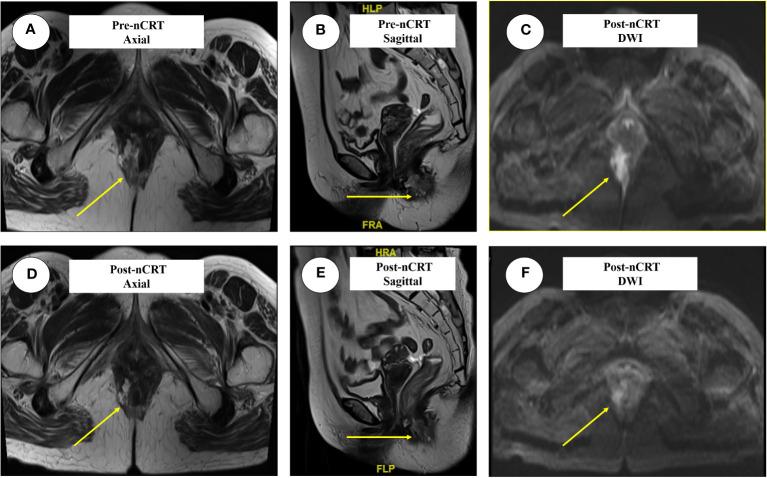

Anal adenocarcinoma combined with perianal Paget's disease (PPD) involving the vulva is rare, and there is no established standard treatment. We present the case of a 69-year-old woman with symptoms of intermittent hematochezia and perianal discomfort for 7 months. Upon examination, we discovered a plaque-like hard mass on the right posterior wall of the anal canal, which extended to encompass the anus and dentate line. The lesion skin also extended forward from the gluteal groove, involving the bilateral labial area. Colonoscopy revealed an extensive protruding lesion on the dentate line, which was confirmed as anal adenocarcinoma (mrT4N0M0). The presence of Paget's cells in perianal and vulvar skins led to the diagnosis of PPD. The strategy of neoadjuvant chemoradiotherapy (nCRT) followed by radical surgery was then made after multi-disciplinary discuss. The scope and extent of perianal and vulvar disease were significantly diminished after nCRT. The patient underwent laparoscopic abdominoperineal resection and vulvar lesion resection, confirming the diagnosis of anal adenocarcinoma (ypT2N0). No evidence of tumor cells was found in perianal and vulvar skin, indicating a complete response. The patient is regularly monitored without recurrence or metastasis.

肛管腺癌合并累及外阴的肛周佩吉特病(PPD)较为罕见,目前尚无既定的标准治疗方法。我们报告了一例69岁女性患者,她有间歇性便血和肛周不适症状达7个月。经检查,我们在肛管右后壁发现一个斑块状硬块,该硬块延伸至肛门和齿状线。病变皮肤还从臀沟向前延伸,累及双侧阴唇区域。结肠镜检查显示齿状线处有广泛的突出病变,确诊为肛管腺癌(mrT4N0M0)。肛周和外阴皮肤中存在佩吉特细胞,从而诊断为PPD。经过多学科讨论后,制定了新辅助放化疗(nCRT)后行根治性手术的策略。nCRT后,肛周和外阴疾病的范围和程度明显缩小。患者接受了腹腔镜腹会阴切除术和外阴病变切除术,确诊为肛管腺癌(ypT2N0)。在肛周和外阴皮肤中未发现肿瘤细胞迹象,表明完全缓解。患者接受定期监测,无复发或转移。